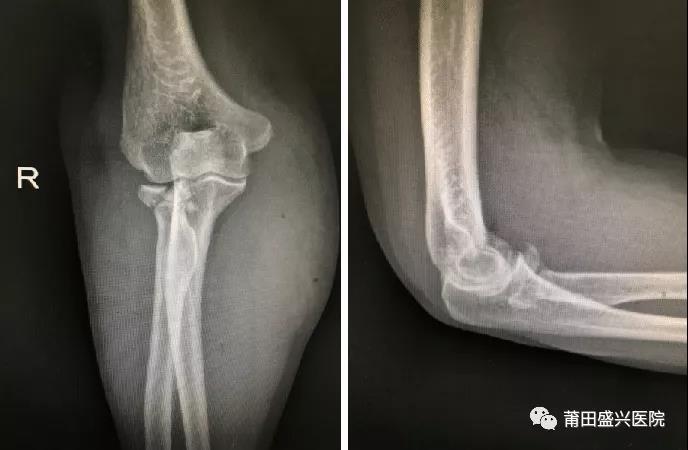

對于成人橈骨頭骨折Mason III型來(lái)說(shuō),橈骨頭就成為維持肘關(guān)節軸向和外翻穩定的主要……